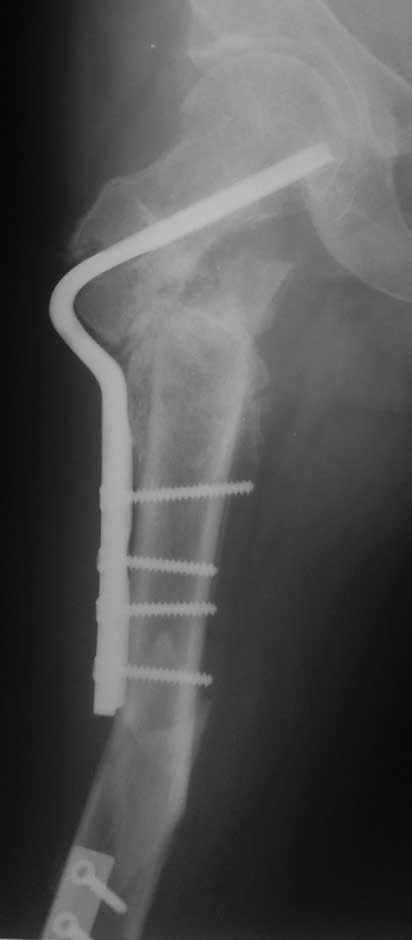

Уважаемые коллеги, помогите пожалуйста с тактикой лечения. Больная 43 лет, подвернув правую ногу, получила простой (А2) перелом правого бедра в с\3, м\у установленными ранее пластинами. В течении 4 недель лечится методом скелетного вытяжения.В анамнезе: в июне 2011г. получила перелом наружного мыщелка правого бедра на фоне консолидированного в порочном варусном положении перелома вертельной зоны (со слов травма 5 лет назад - лечилась консервативно), сопровождающимся укорочением 5 см. В одну операционную сессию выполнен остеосинтез перелома мыщелка бедра Т-образной пластиной и с целью коррекции укорочения выполнена вальгизирующая межвертельная остеотомия с фиксацией клинковой пластиной.На наш взгляд, наиболее простым является накостный остеосинтез диафизарного перелома по передней поверхности бедра, но смущает необходимость образования в последующем дополнительного кожного рубца. Пожалуйста, может быть у Вас есть другие мнения. Зарание благодарен. С уважением А.Гринь. ОКБ №2 г.Тюмень.

Вообще-то кожный рубец - это ерунда. Тут есть куда более серьезные проблемы - в области межвертельной остеотомии и медиализирован диафиз зря, и сращение проблематично. Так что, наверно, можно воспользоваться подвернувшимся поводом, удалить пластинки, да синтзировать стержнем закрыто, улучшив положение в вертельной области (как - это отдельная проблема). Попутно рассеются опасения насчет дополнительного кожного рубца в середине бедра.

М\У пластины - наверное слово между пластинами, зачем такие сокращения не понятно. Хотя боковых рентгенограмм нет, можно предполагать что мыщелки бедра с июня вероятно в стадии активноой консолидации. В связи с чем в большей мере согласен с Челноковым А.Н. и удалил бы старые фиксаторы перейдя к блокироанному бедренному гвоздю с дистальной полиаксиальной фиксацией. Если есть какие-нибудь осложняющие моменты то аппарат Илизарова более выгоден пациенту, чем третья пластина.

На снимке положение клинка идеальное, но шейка в ротации. Из-за неправильного расчета остеотомии не удалось латерализовать диафиз, и конечность находится в чрезмерном вальгусе. При укорочении с вальгусом увеличивает стресс в зоне между пластинами, и конструкция не выдерживает, и при малой травме может осложниться стрессовым переломом.

Из возможных операций: я бы предложил провести ретроградную фиксацию бедра после удаления дистальной пластины. При отсутствии полного сращения перелома можно установить пару шурупов спереди и сзади гвоздя, или можно оставить укороченный вариант пластины.

Гвоздь подвести под вертел, и оставить проксимальный винт, а остальные шурупы могут быть через один кортекс. Идеально установить "стоппер", который укоротит клинок и латерализует диафиз. Создаст компрессию!

Из бокового "субвастусного" доступа можно уложить пластину спереди, но тогда надо подождать с нагрузкой. Провокационный антеградный вариант технически сложен, но тогда теряется преимущества сколжения клинка в шейке, и потом клинок не разрушает, как остальные дивайсы, костную структуру в головке.